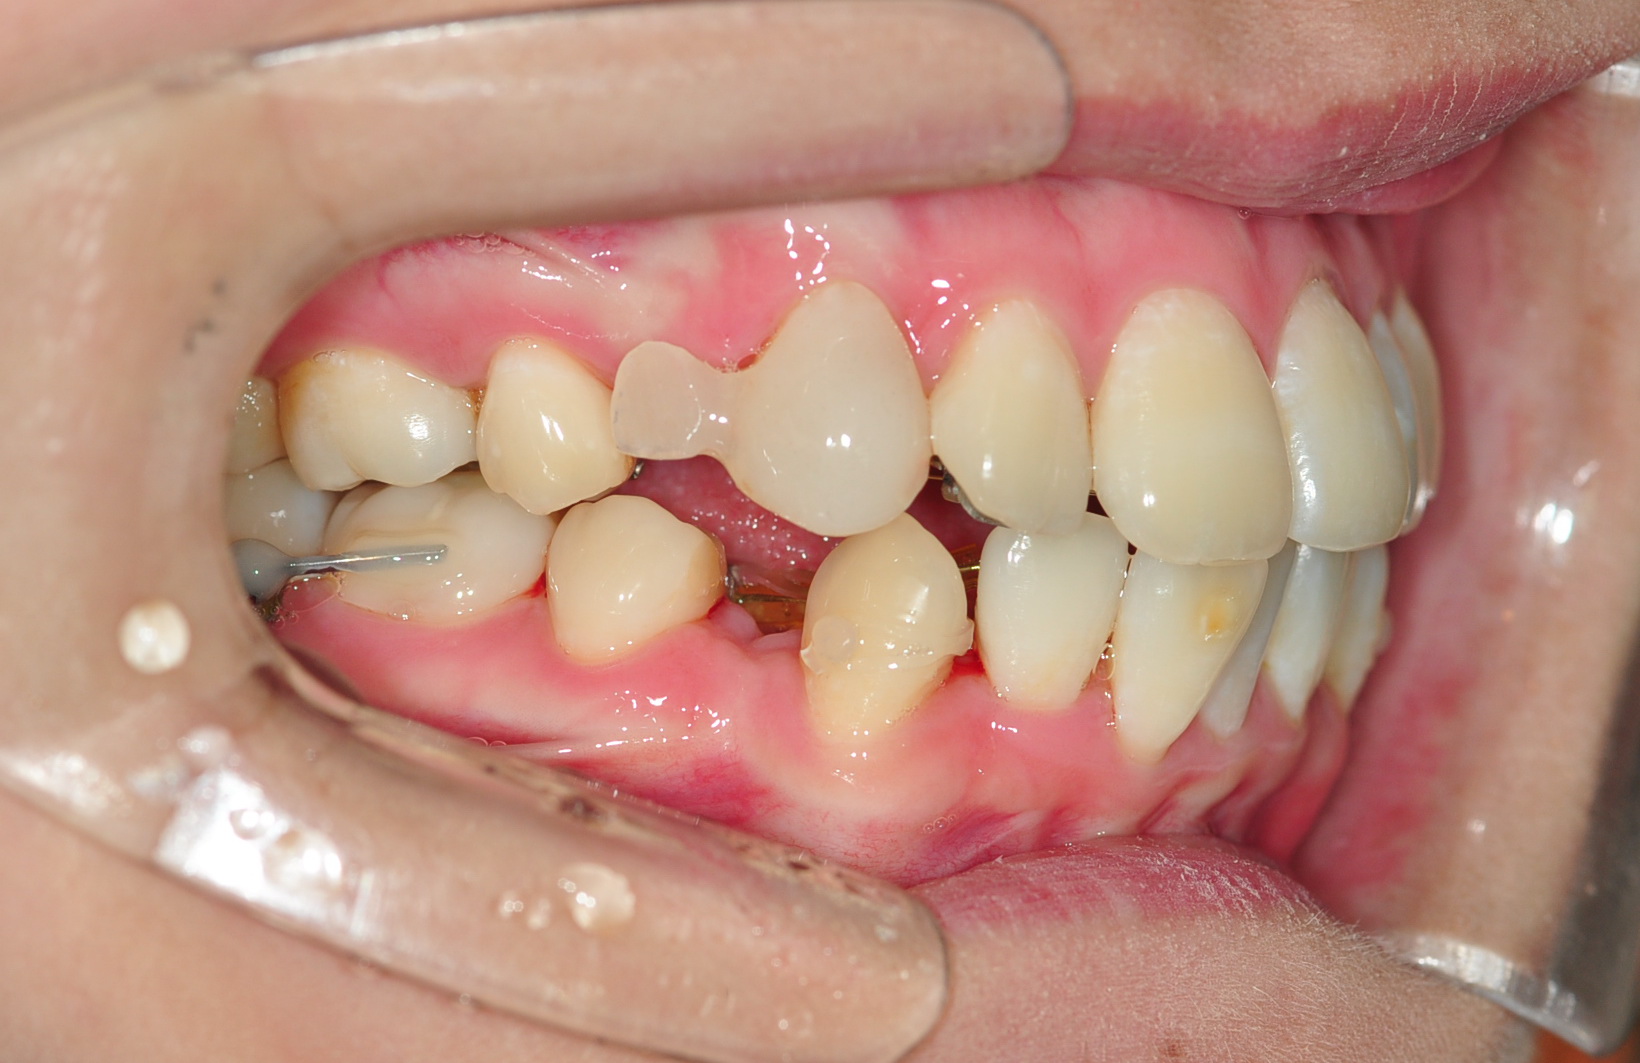

이번 오라픽스 치아교정 치료는 고무줄을 파워체인으로 교체하는 것과

상악에 심어두었던 스크류와 상악어금니를 연결하는 치료를 하였어용

두달 전쯤 치아교정 장치 브라켓이 떨어졌던 어금니와 연결하였답니당

원장선생님께서 치아의 이동상태를 보시고는 잘 이동하고 있다고 하시더라구요 ><